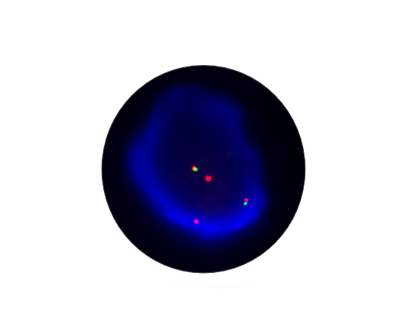

This is a biology laboratory

Molecular diagnostics is a rapidly evolving field that encompasses a complex endeavor, with multiple regulatory pathways to consider and numerous approaches to development and commercialization. It plays a pivotal role in investigating human, viral, and microbial genomes and the products they encode. The molecular laboratory performs molecular diagnostic testing for nucleic acid targets in patient samples. Due to the incredible sensitivity and specificity associated with the use of molecular assays, molecular laboratories have the capability to more rapidly and accurately identify pathogens than laboratories that use more conventional methods.